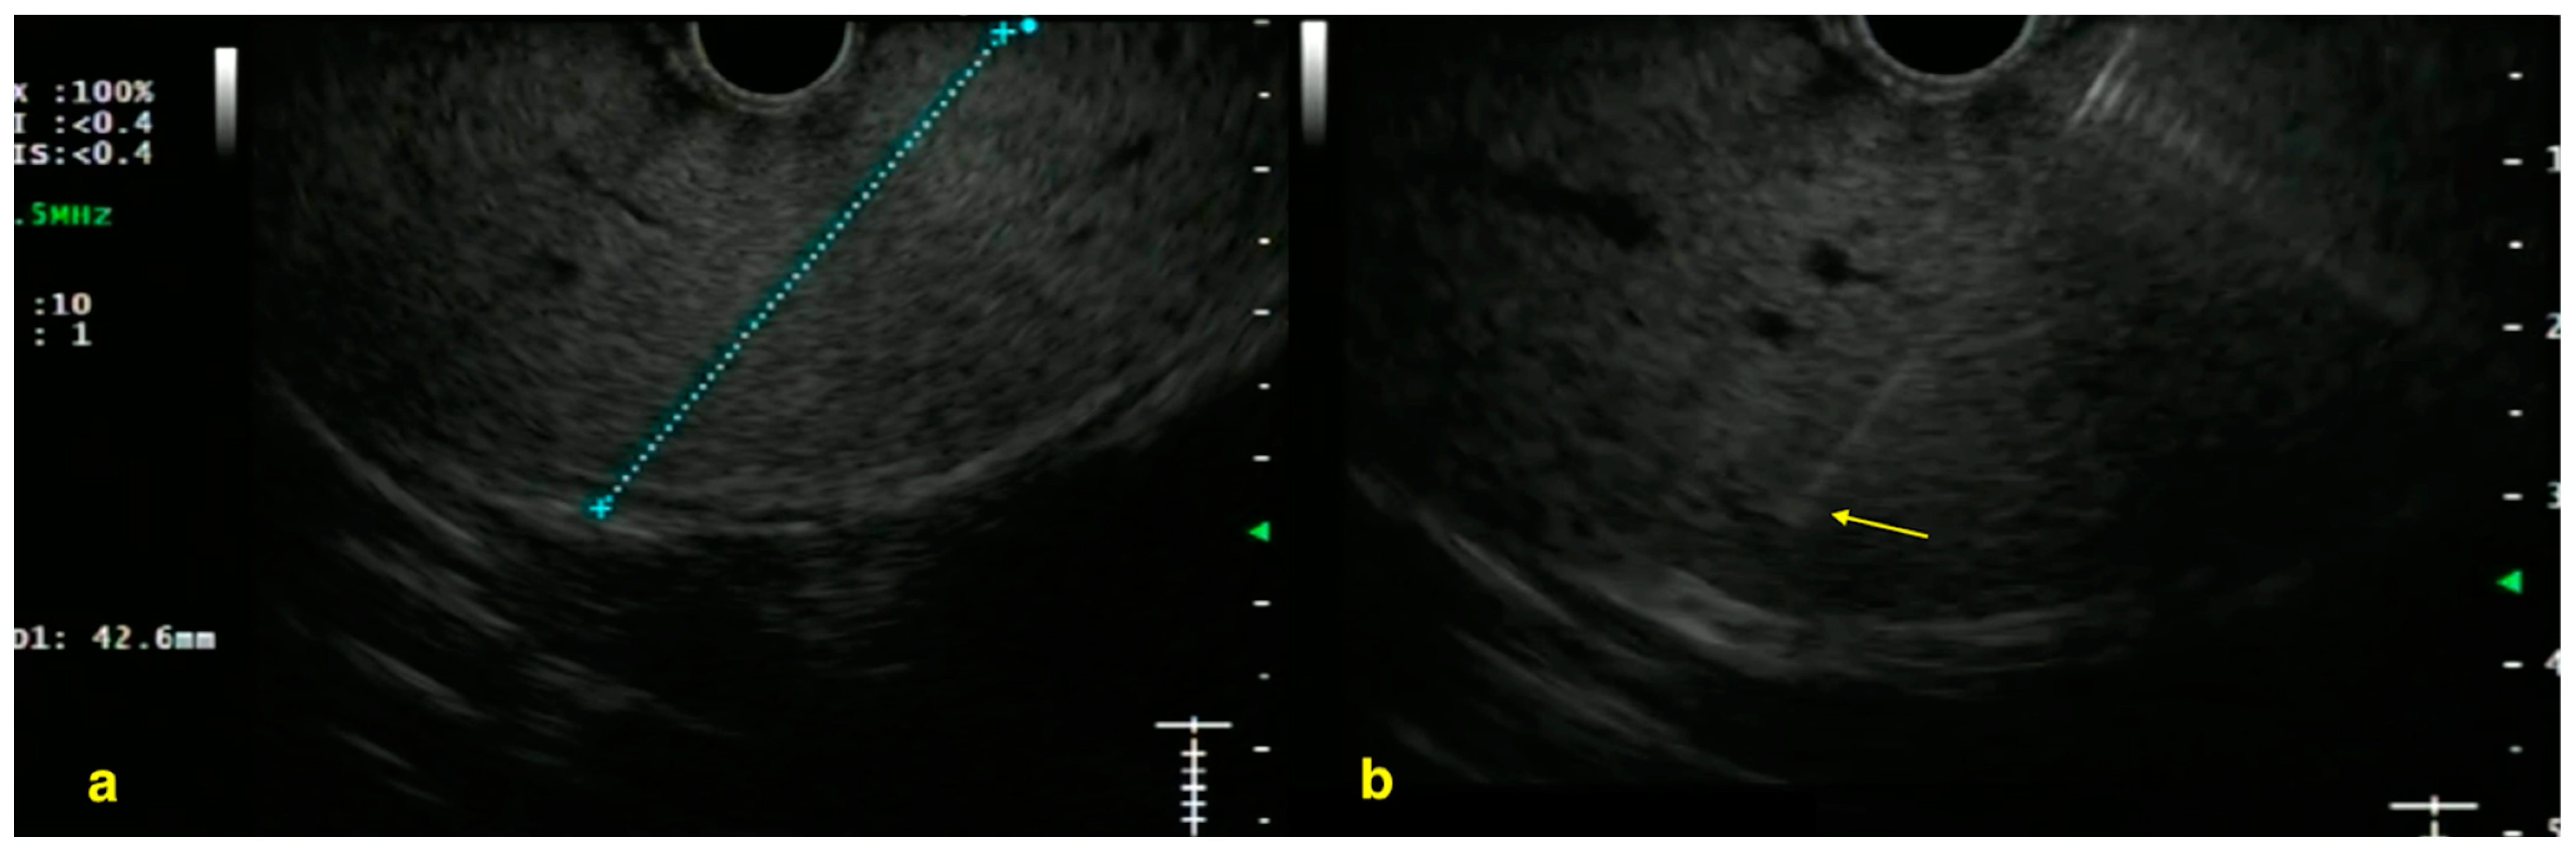

4. Liver Biopsy